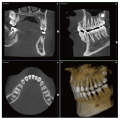

歯科用3DCT